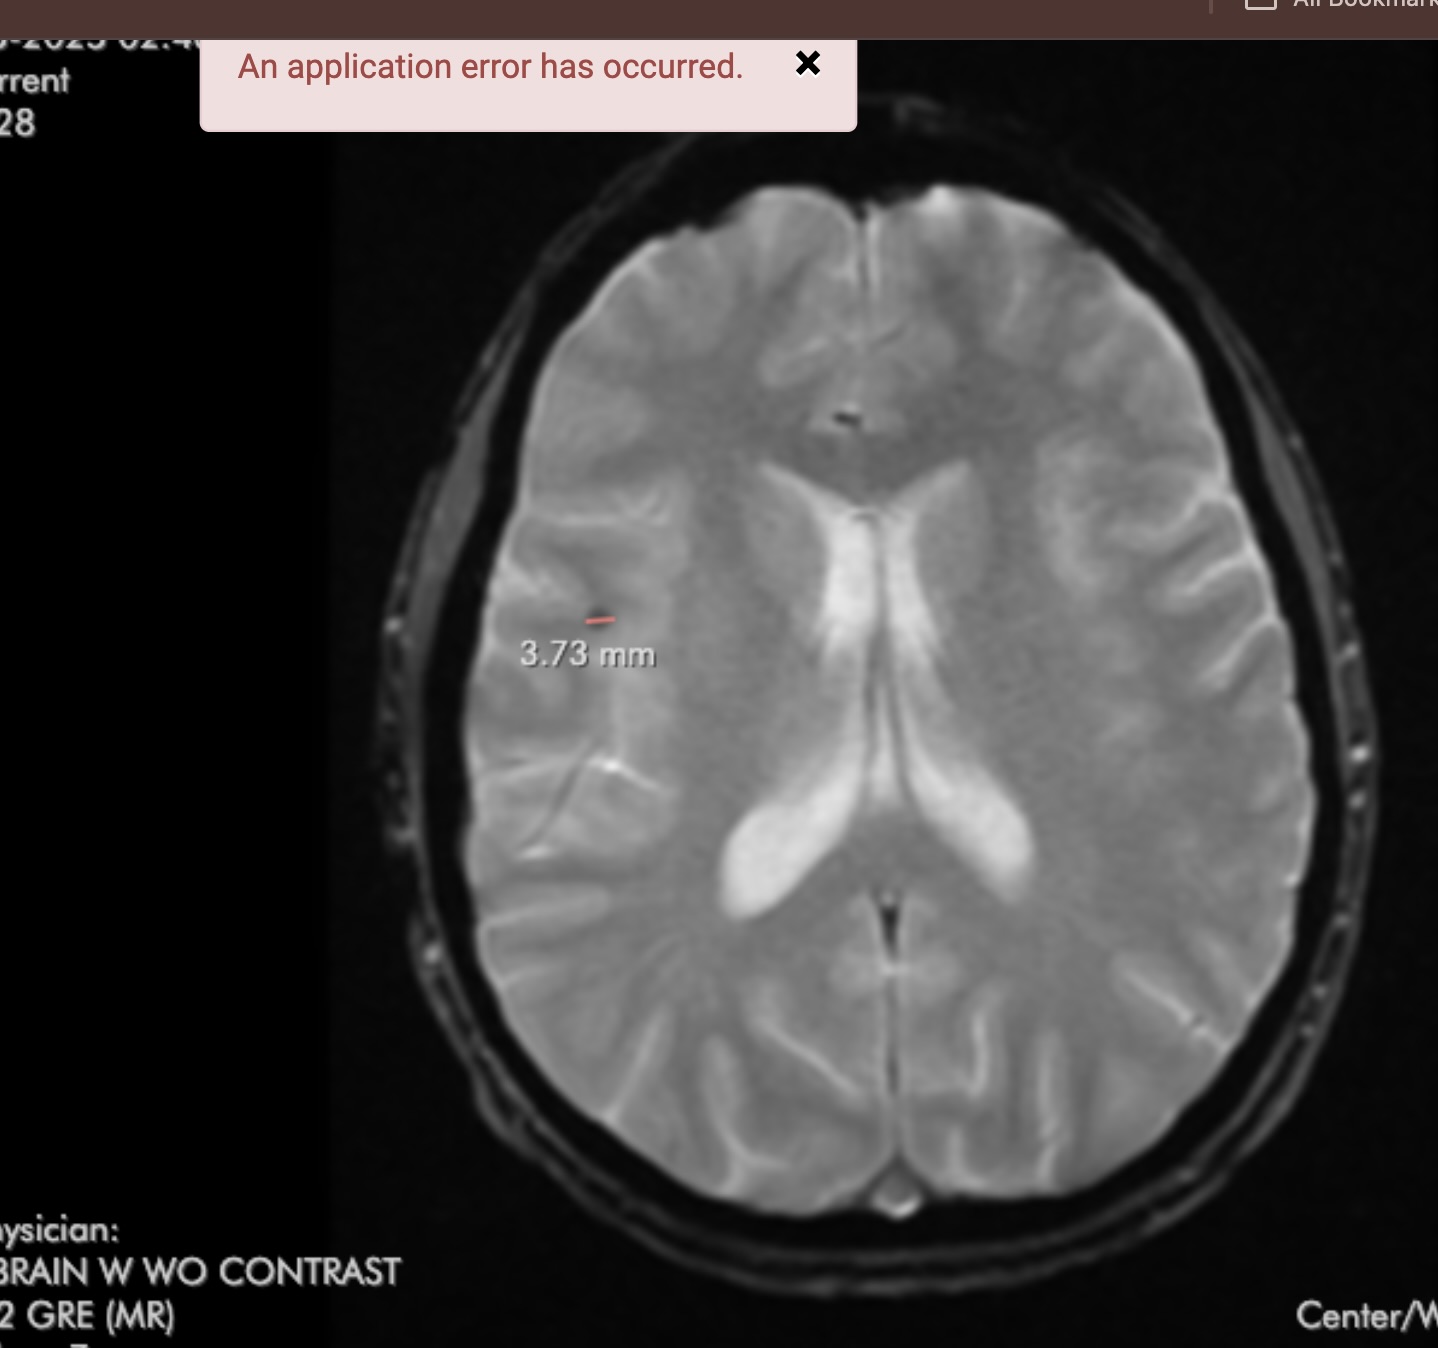

It looks to me like what is called an ‘artifact’ or glitch in the recording process. There is NO WAY a catheter, or probe, etc. would have such a circular looking path through all those layers of cortex, midbrain, corpus callosum, etc. Also bear in mind that MRIs are rendered one slice at a time, and the likelihood of such an object aligning ‘perfectly’ with the slice geometry along such a long distance, is just impossible.

Thank you! It appears in several sequences so it was concerning, and aligned with a marked artifact noted on another view.

Obviously an artifact if it appears on multiple image slices. Possibly change which facility / MRI machine you are using.